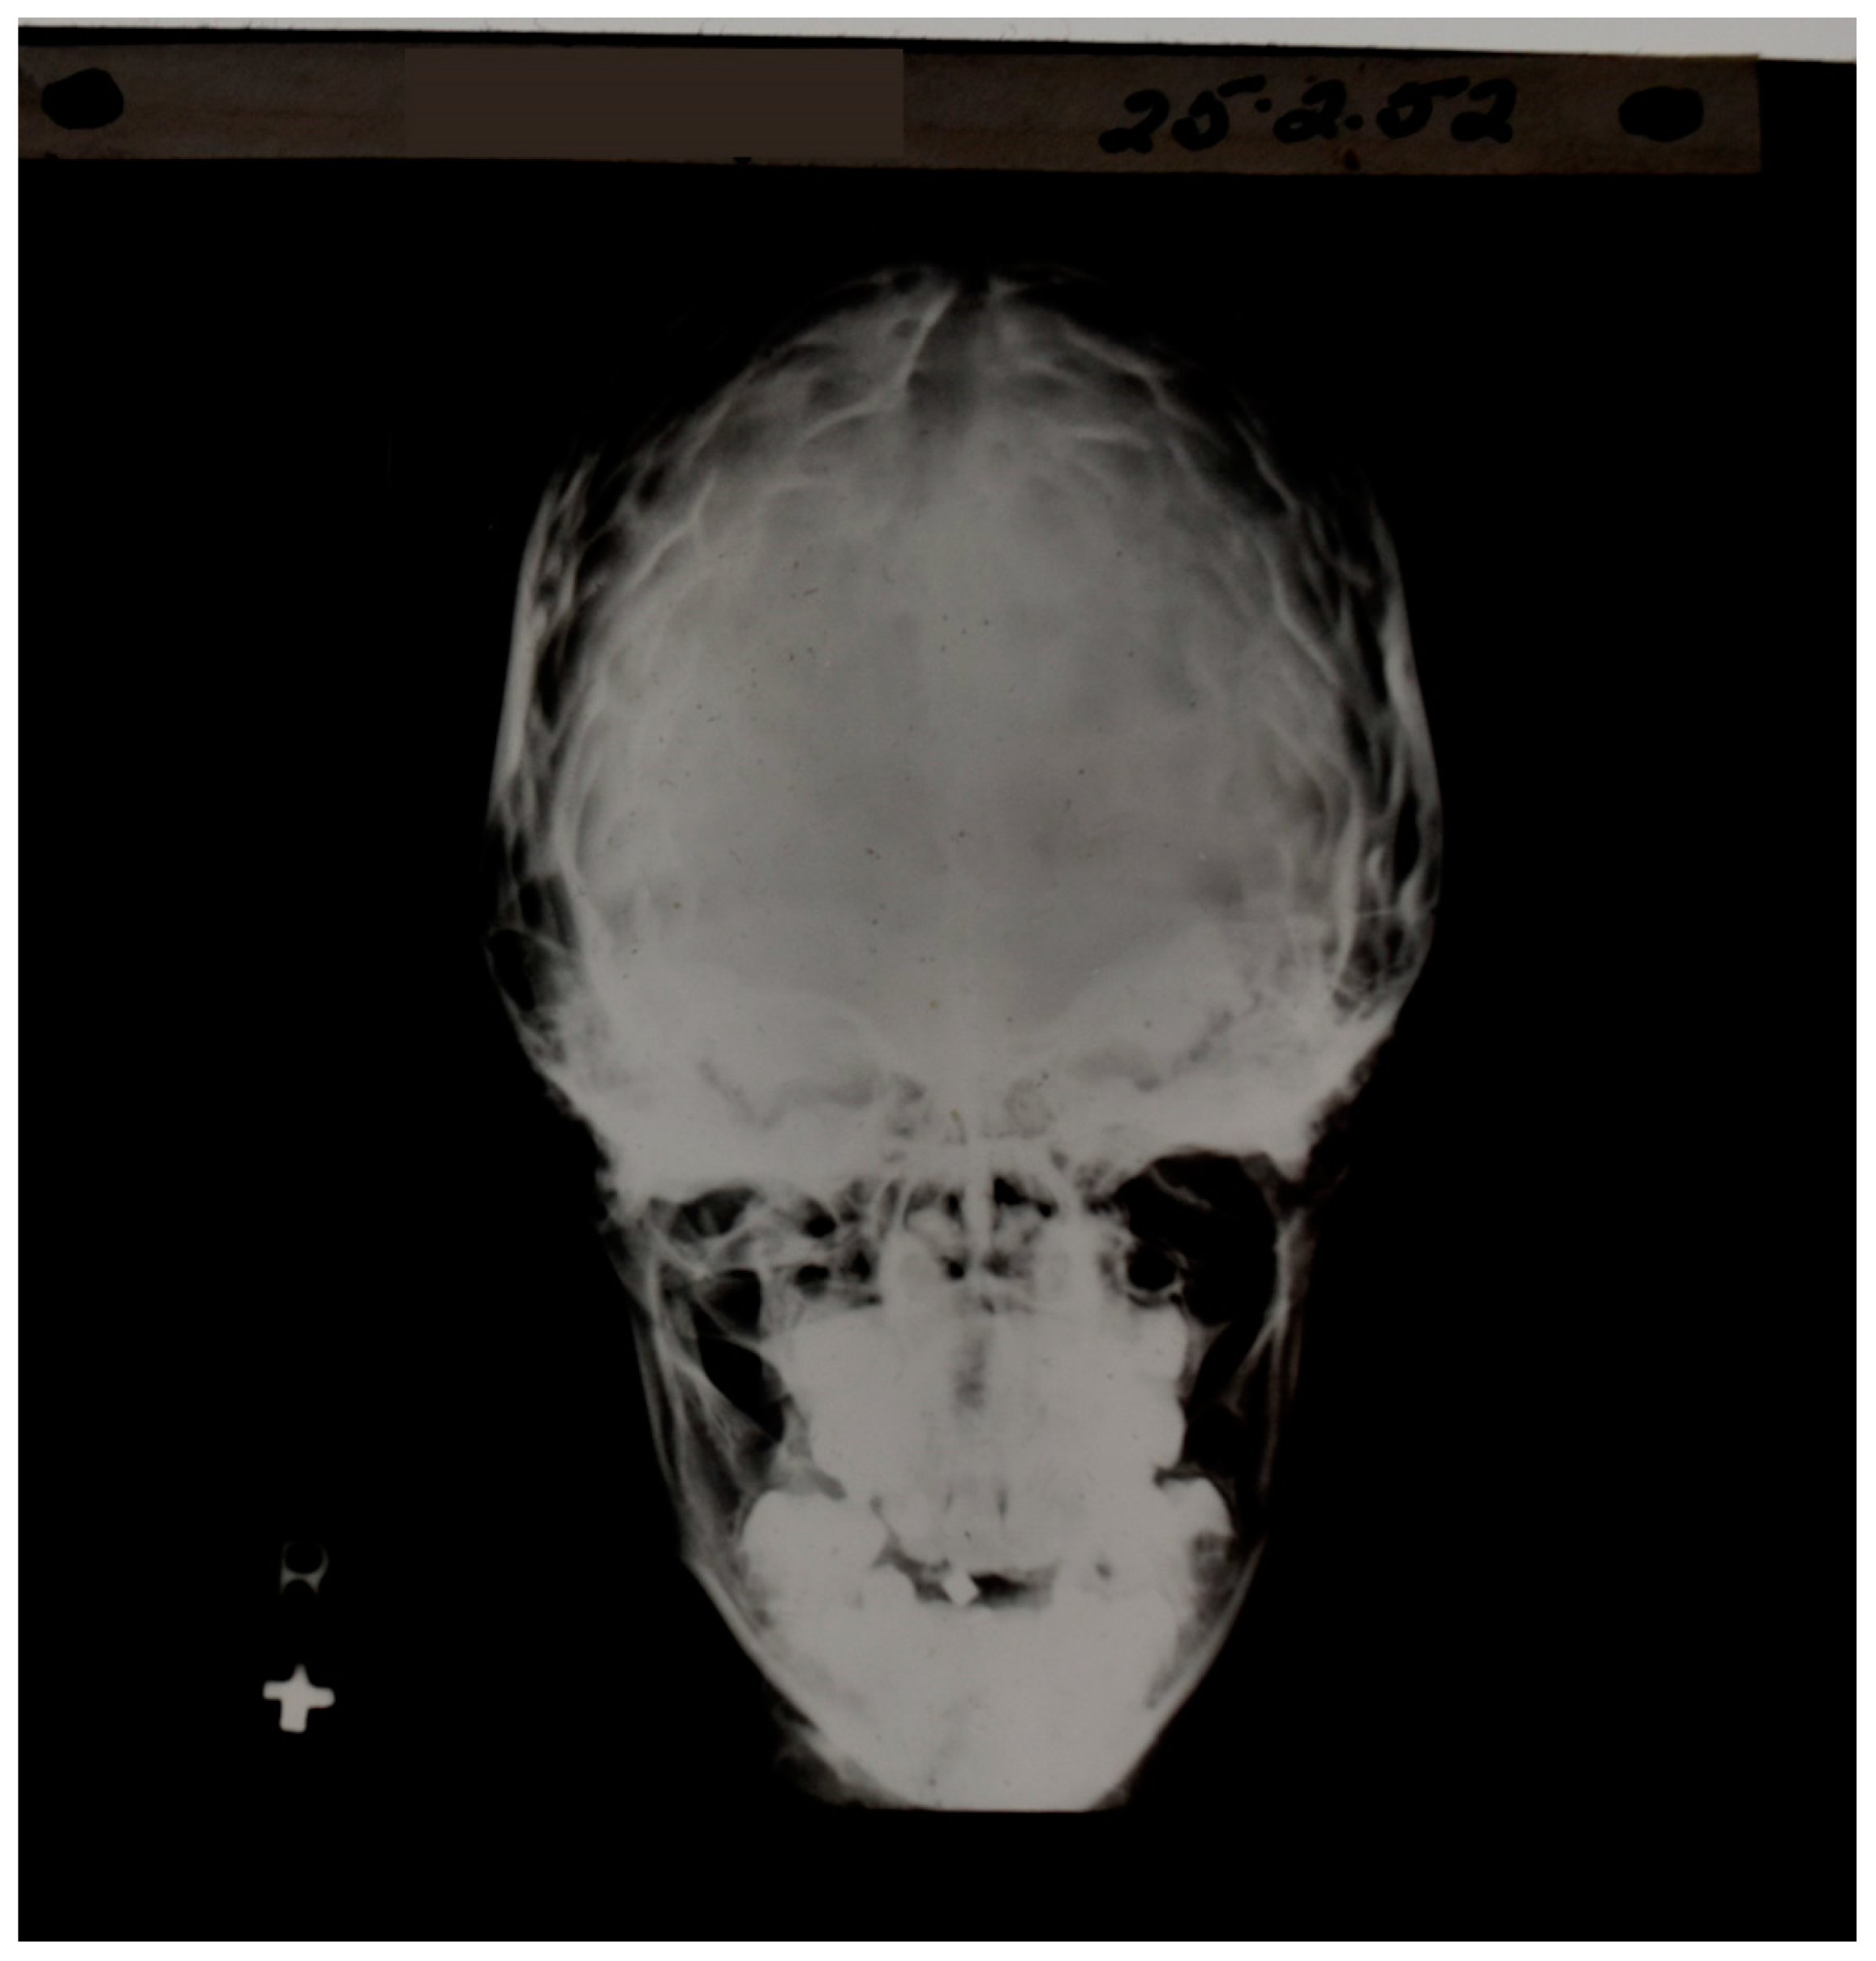

In plain radiographs of the head, contrast could be seen between bone of different thickness, but the soft tissue of the brain itself could not specifically be seen (Figure 2). If air was substituted for CSF, contrast could be created between the ventricular system (now containing air rather than CSF) and the surrounding brain. This technique, which was developed by Walter Dandy in 1918–1919, was used diagnostically to recognize disease of the brain by displacement or distortion of the ventricular system and/or subarachnoid space in air studies of the brain [2,3] as shown in Figure 3.

Figure 2.

Early skull X-ray. Contrast is seen between bone and air as well as between bone of different thicknesses; however, the soft tissue of the brain is not directly observable.